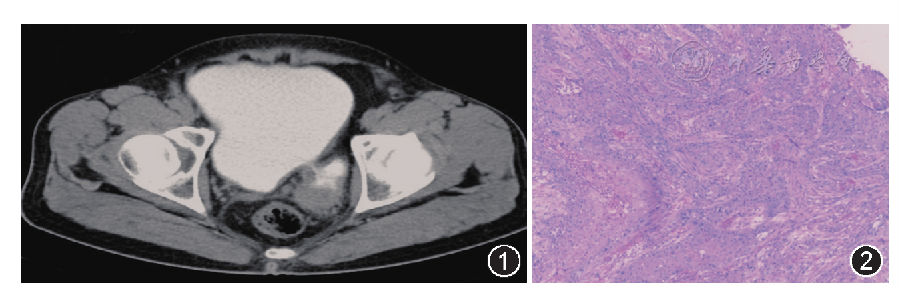

检查:尿潜血(3+),尿白细胞(3+),尿蛋白(+)。B超检查示前列腺增生伴钙化,膀胱憩室。尿流率检测:最大尿流率14.6 ml/min。盆腔CT检查

:膀胱左后方憩室,憩室壁欠规整、增厚(图1)。

图1盆腔CT增强:膀胱充盈良好,左后方可见囊袋状突起,囊壁欠规整,可见造影剂进入;

图2膀胱憩室化生性癌,部分区域为浸润性高级别尿路上皮癌,部分区域为鳞状细胞癌,部分区域为骨肉瘤(HE ×40)

:灰白色囊壁样组织,大小约8.0 cm×5.0 cm×0.4 cm,囊内壁光滑,局灶咖啡色。镜下见(膀胱憩室)浸润性低分化尿路上皮癌累及送检膀胱憩室壁全层。于2周后行根治性全膀胱切除术+双侧输尿管皮肤造口术。病理检查:膀胱约8.0 cm×7.0 cm×5.0 cm,膀胱左下壁厚、质硬,切面灰白,质硬区范围4.0 cm×3.0 cm;见完整双侧精囊腺及前列腺,左盆腔淋巴结2枚。镜下见膀胱憩室化生性癌,部分区域为浸润性高级别尿路上皮癌,部分区域为鳞状细胞癌,部分区域为骨肉瘤

(图2);癌组织紧邻左侧精囊腺,左输精管及右精囊腺未见癌浸润;前列腺未见癌浸润;左盆腔淋巴结2枚未见癌转移。免疫组化染色检查:CKp(++),CK7(+++),P40(+),CK5/6(+)。